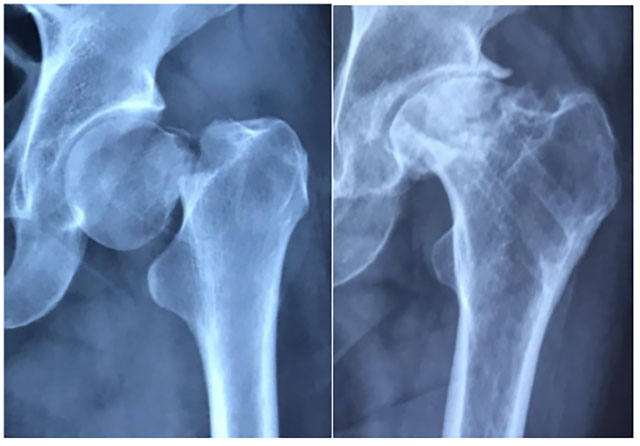

什么是股骨颈骨折?

股骨颈是股骨头和股骨粗隆之间连接的较细的部分。

股骨颈骨折是髋部最常见的骨折,中老年人多见。中青年人股骨颈骨折也逐年上升,骨折后易出现骨不愈合、骨坏死造成较高的致残率。